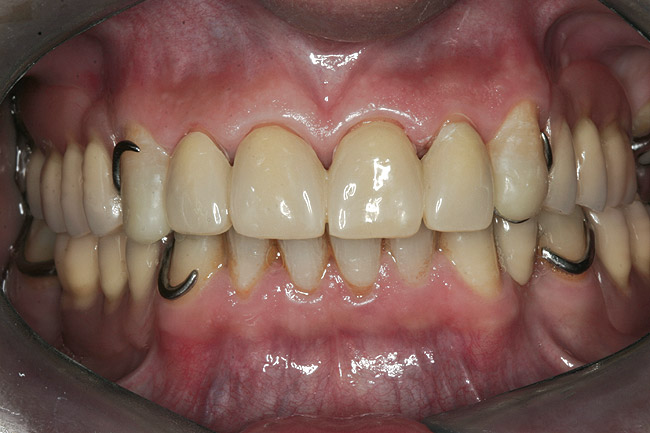

Initial examination revealed a partial edentulous patient with extensive wear of the maxillary anterior teeth and moderate wear in the mandibular teeth (Figure 1, Figure 2, Figure 3 , Figure 4, Figure 5, Figure 6 and Figure 7). The patient's maxillary and mandibular RPDs also showed excessive wear and multiple signs of fractures (Figure 2 and Figure 3). The patient had been wearing a mandibular nightguard for 8 years.

The framework was evaluated intraorally for fit, occlusion, retention, and stability (Figure 13, Figure 14 and Figure 15). With the framework in position, a new maxillo–mandibular relationship record was made with a silicone-based interocclusal record material, and the definitive casts were remounted on the articulator. The framework was returned to the laboratory, and acrylic resin veneers were applied in the esthetic zone and posterior artificial acrylic resin teeth were placed on the framework. The artificial teeth were arranged and tried in to verify esthetics and jaw relation records and to obtain the patient's approval before final processing. The junction between the maxillary natural teeth and the overlay prosthesis was not noticeable during normal speech and function.

Figure 16  Anterior, lateral right, and left view of the maxillary prosthesis teeth try-in.

Figure 16

Figure 17  Details of the maxillary prosthesis finished after the reconstruction of the canines.

Figure 17